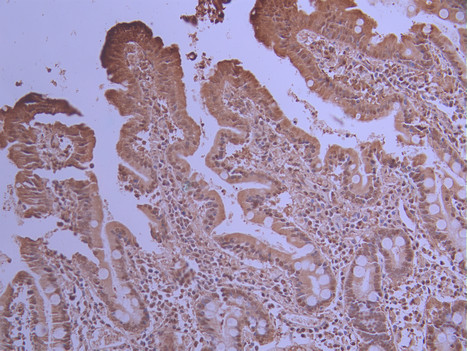

IHC image of CSB-RA140307A0HU diluted at 1:100 and staining in paraffin-embedded human small intestine tissue performed on a Leica BondTM system. After dewaxing and hydration, antigen retrieval was mediated by high pressure in a citrate buffer (pH 6.0). Section was blocked with 10% normal goat serum 30min at RT. Then primary antibody (1% BSA) was incubated at 4°C overnight. The primary is detected by a Goat anti-rabbit polymer IgG labeled by HRP and visualized using 0.05% DAB.